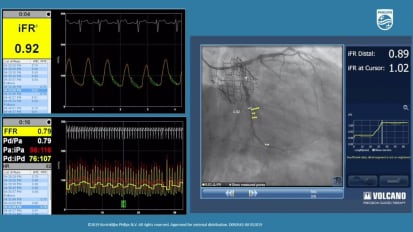

Optimizing coronary stenting: the role of IVUS in today’s precision PCI

Hear Dr. Jimmy Kerrigan and Dr. Lorenzo Azzalini as they discuss the role of intravascular imaging in their practice and how the utility of routine IVUS can guide procedural planning and optimization of treatment. This program highlights the clinical utility and benefits of IVUS through a review of current clinical data, including the ULTIMATE trial, and through demonstration and discussion of IVUS in a variety of clinical scenarios.